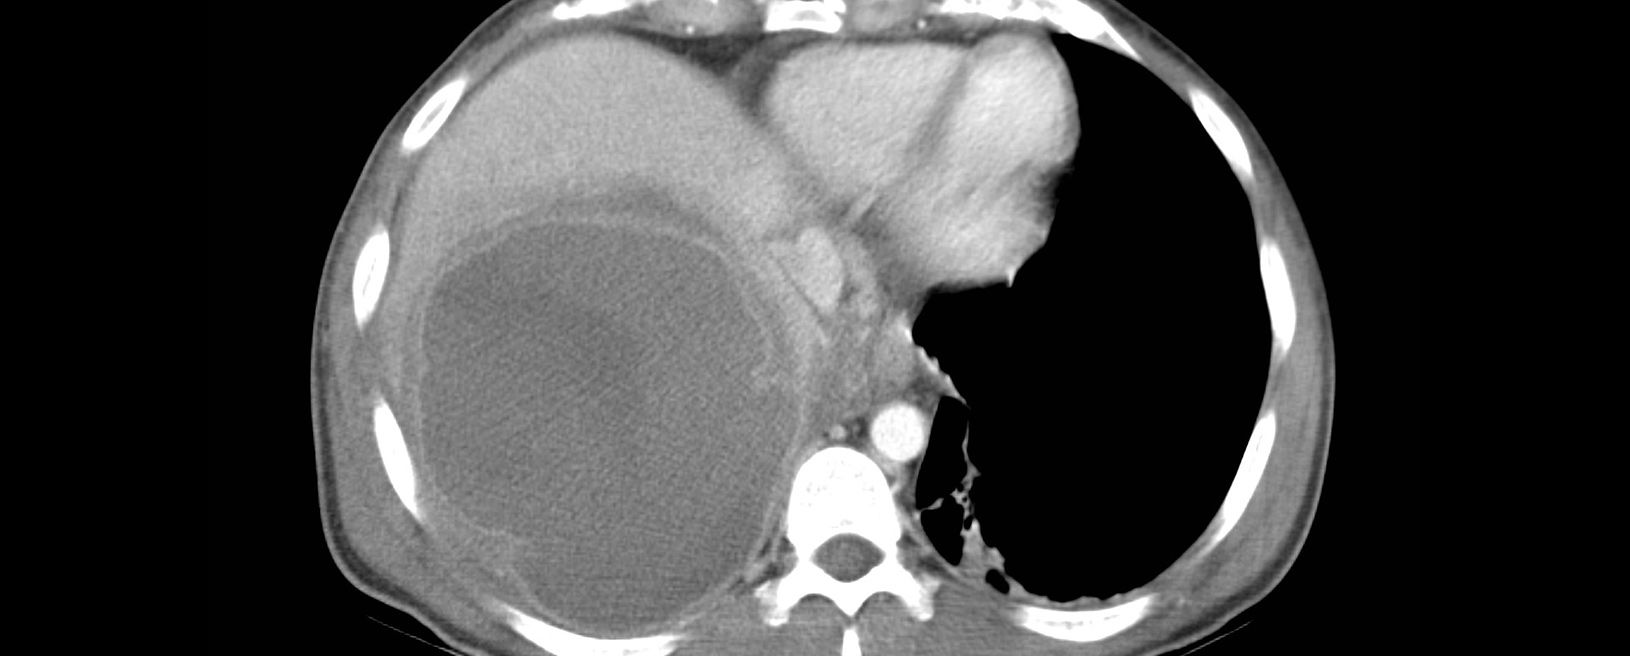

1. USH hepático, TC, IRM

1. Lesiones redondas-ovaladas no homogéneas baja densidad, centros hipoecoicos